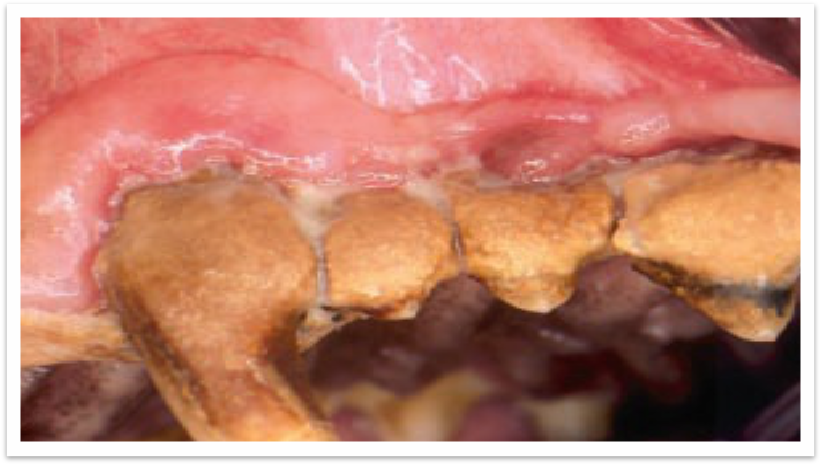

后期阶段

活动篇| 啊,让你的宠物张张嘴

3级 CH严重   >2/3牙齿表面,且发展到牙龈下